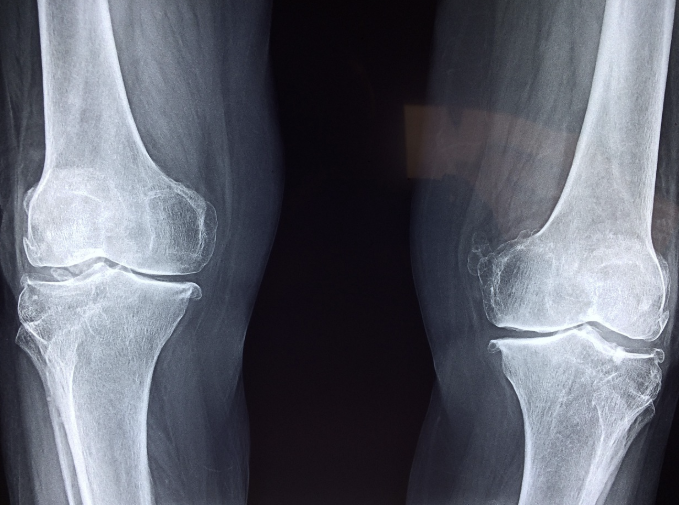

중년에 접어들면 자연스럽게 근육량이 감소하고, 관절의 유연성이 떨어지면서 체지방이 증가할 가능성이 높아집니다. 이를 예방하기 위해서는 젊을 때부터 건강한 생활습관을 유지하는 것이 중요합니다.

✔ 프로코사 글루코사민

- 인셀리전스 기술 적용으로 관절 건강 및 연골 생성 지원

- 1,500mg의 식물성 글루코사민염삼연 함유